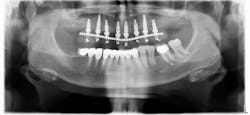

In 1998, I started to place narrow implants not only in the anterior areas, but also in posterior maxillary and mandibular regions in order to replace premolars and molars. I began to treat partially edentulous patients with a high success rate.

I immediately found an increasing number of cases to be treated in this way. From 1998 to 2008, I placed 824 narrow implants, with a success rate of 98.5%. From 2009 to 2016, I placed 4,266 narrow implants, multiplying the number of narrow implants by nearly six.

Placement of narrow implants. In a full-arch restoration in the presence of alveolae and thin ridges, narrow implants allow the placement of more biomaterial in the alveolae for ridge preservation. Bone grafting will be avoided in the presence of the ridges.